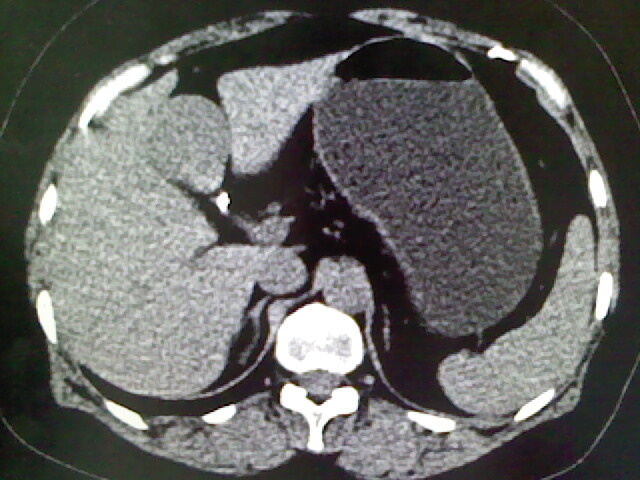

以下是引用卜一在2009-4-2 13:26:00的发言:[br]胆囊颈部结石伴胆囊炎!另:建议增强,待除外肝内占位及胆囊占位!

以下是引用liaoqiang在2009-4-2 16:23:00的发言:[br]胆囊是否切除?胆囊颈区致密影考虑金属夹?结石?肝脏右叶低密度影,考虑增强。